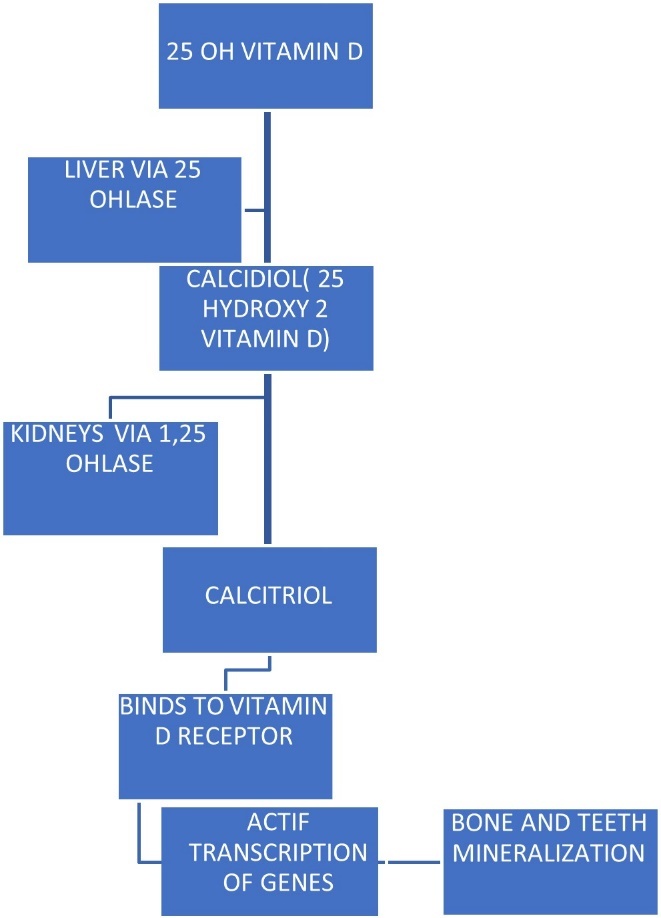

In its native form, vitamin D is inactive (25-hydroxy vitamin D). Its activation in the liver and kidneys depends on two enzymes, namely 25- hydroxylase and 1-alpha-hydroxylase 7, 8. In its active form, namely calcitriol (1,25-hydroxy-3 vitamin D), vitamin D enables the fixation of calcium and phosphorus into the bone and teeth through the formation of a phosphate complex, allowing for mineralization 6. Table 1

Table 1.Activation and function of vitamin D